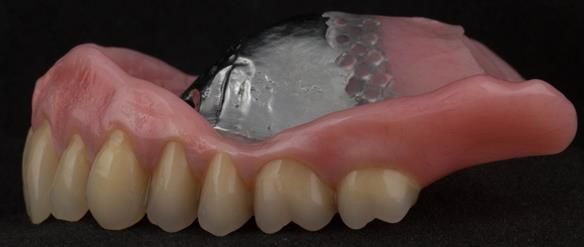

This newsletter describes in step by step detail the transition from acrylic based immediate dentures to metal based definitive dentures.

- Definitive dentures (Mk 2) – complete upper metal reinforced and lower cobalt chromium based partial of hygienic Scandinavian design to be made 9 - 12 months after extractions of all upper teeth and LR5 and LL4